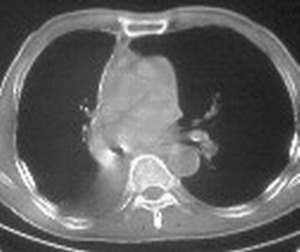

影像特征很象,包裹性胸腔积液,建议楼主测ct值鉴别.

ct值约12hu

右肺下野后部均匀低密度影,边缘锐利,前缘外突(不支持肺不张),纵隔内未见明显肿大淋巴结,右下肺门结构显示欠清,临床资料太过简单,考虑右侧后胸部包裹性积液。其他待排。建议密切结合临床其他检查。

ct值12,包裹性胸腔积液,